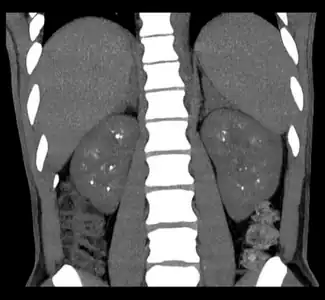

Non-contrast coronal CT depicts nephrocalcinosis. -

Nephrocalcinosis is diagnosed for the most part by imaging techniques. The imagings used are ultrasound (US), abdominal plain film and CT imaging.[11] Of the 3 techniques CT and US are the more preferred. Nephrocalcinosis is considered present if at least two radiologists make the diagnosis on US and/or CT. In some cases a renal biopsy is done instead if imaging is not enough to confirm nephrocalcinosis. Once the diagnosis is confirmed additional testing is needed to find the underlying cause because the underlying condition may require treatment for reasons independent of nephrocalcinosis.[11] These additional tests will measure serum, electrolytes, calcium, and phosphate, and the urine pH.[11] If no underlying cause can be found then urine collection should be done for 24 hours and measurements of the excretion of calcium, phosphate, oxalate, citrate, and creatinine are looked at.[11]